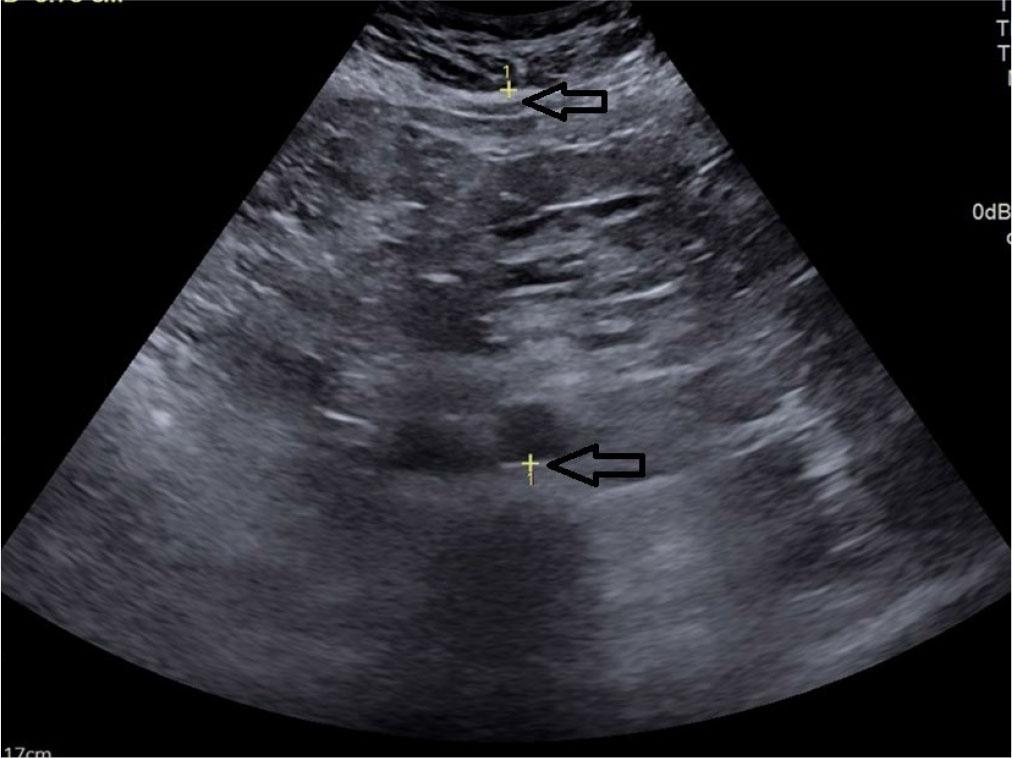

Subcutaneous fat thickness (SCFT) – the minimum thickness of fat located between the linea alba and the interface of the subcutaneous fat with the dermal layer of the skin(22) (Fig. 3).

Transverse grey scale ultrasonography of the abdomen showing measurement of subcutaneous fat thickness denoted by calipers

Visceral fat thickness (VFT) – the distance between the posterior border of the rectus abdominis muscle and the anterior wall of the aorta, measured perpendicular to the aorta at the level of the umbilicus(21) (Fig. 4).

Transverse grey scale ultrasound of the abdomen showing measurement technique for visceral fat thickness denoted by calipers (arrow)